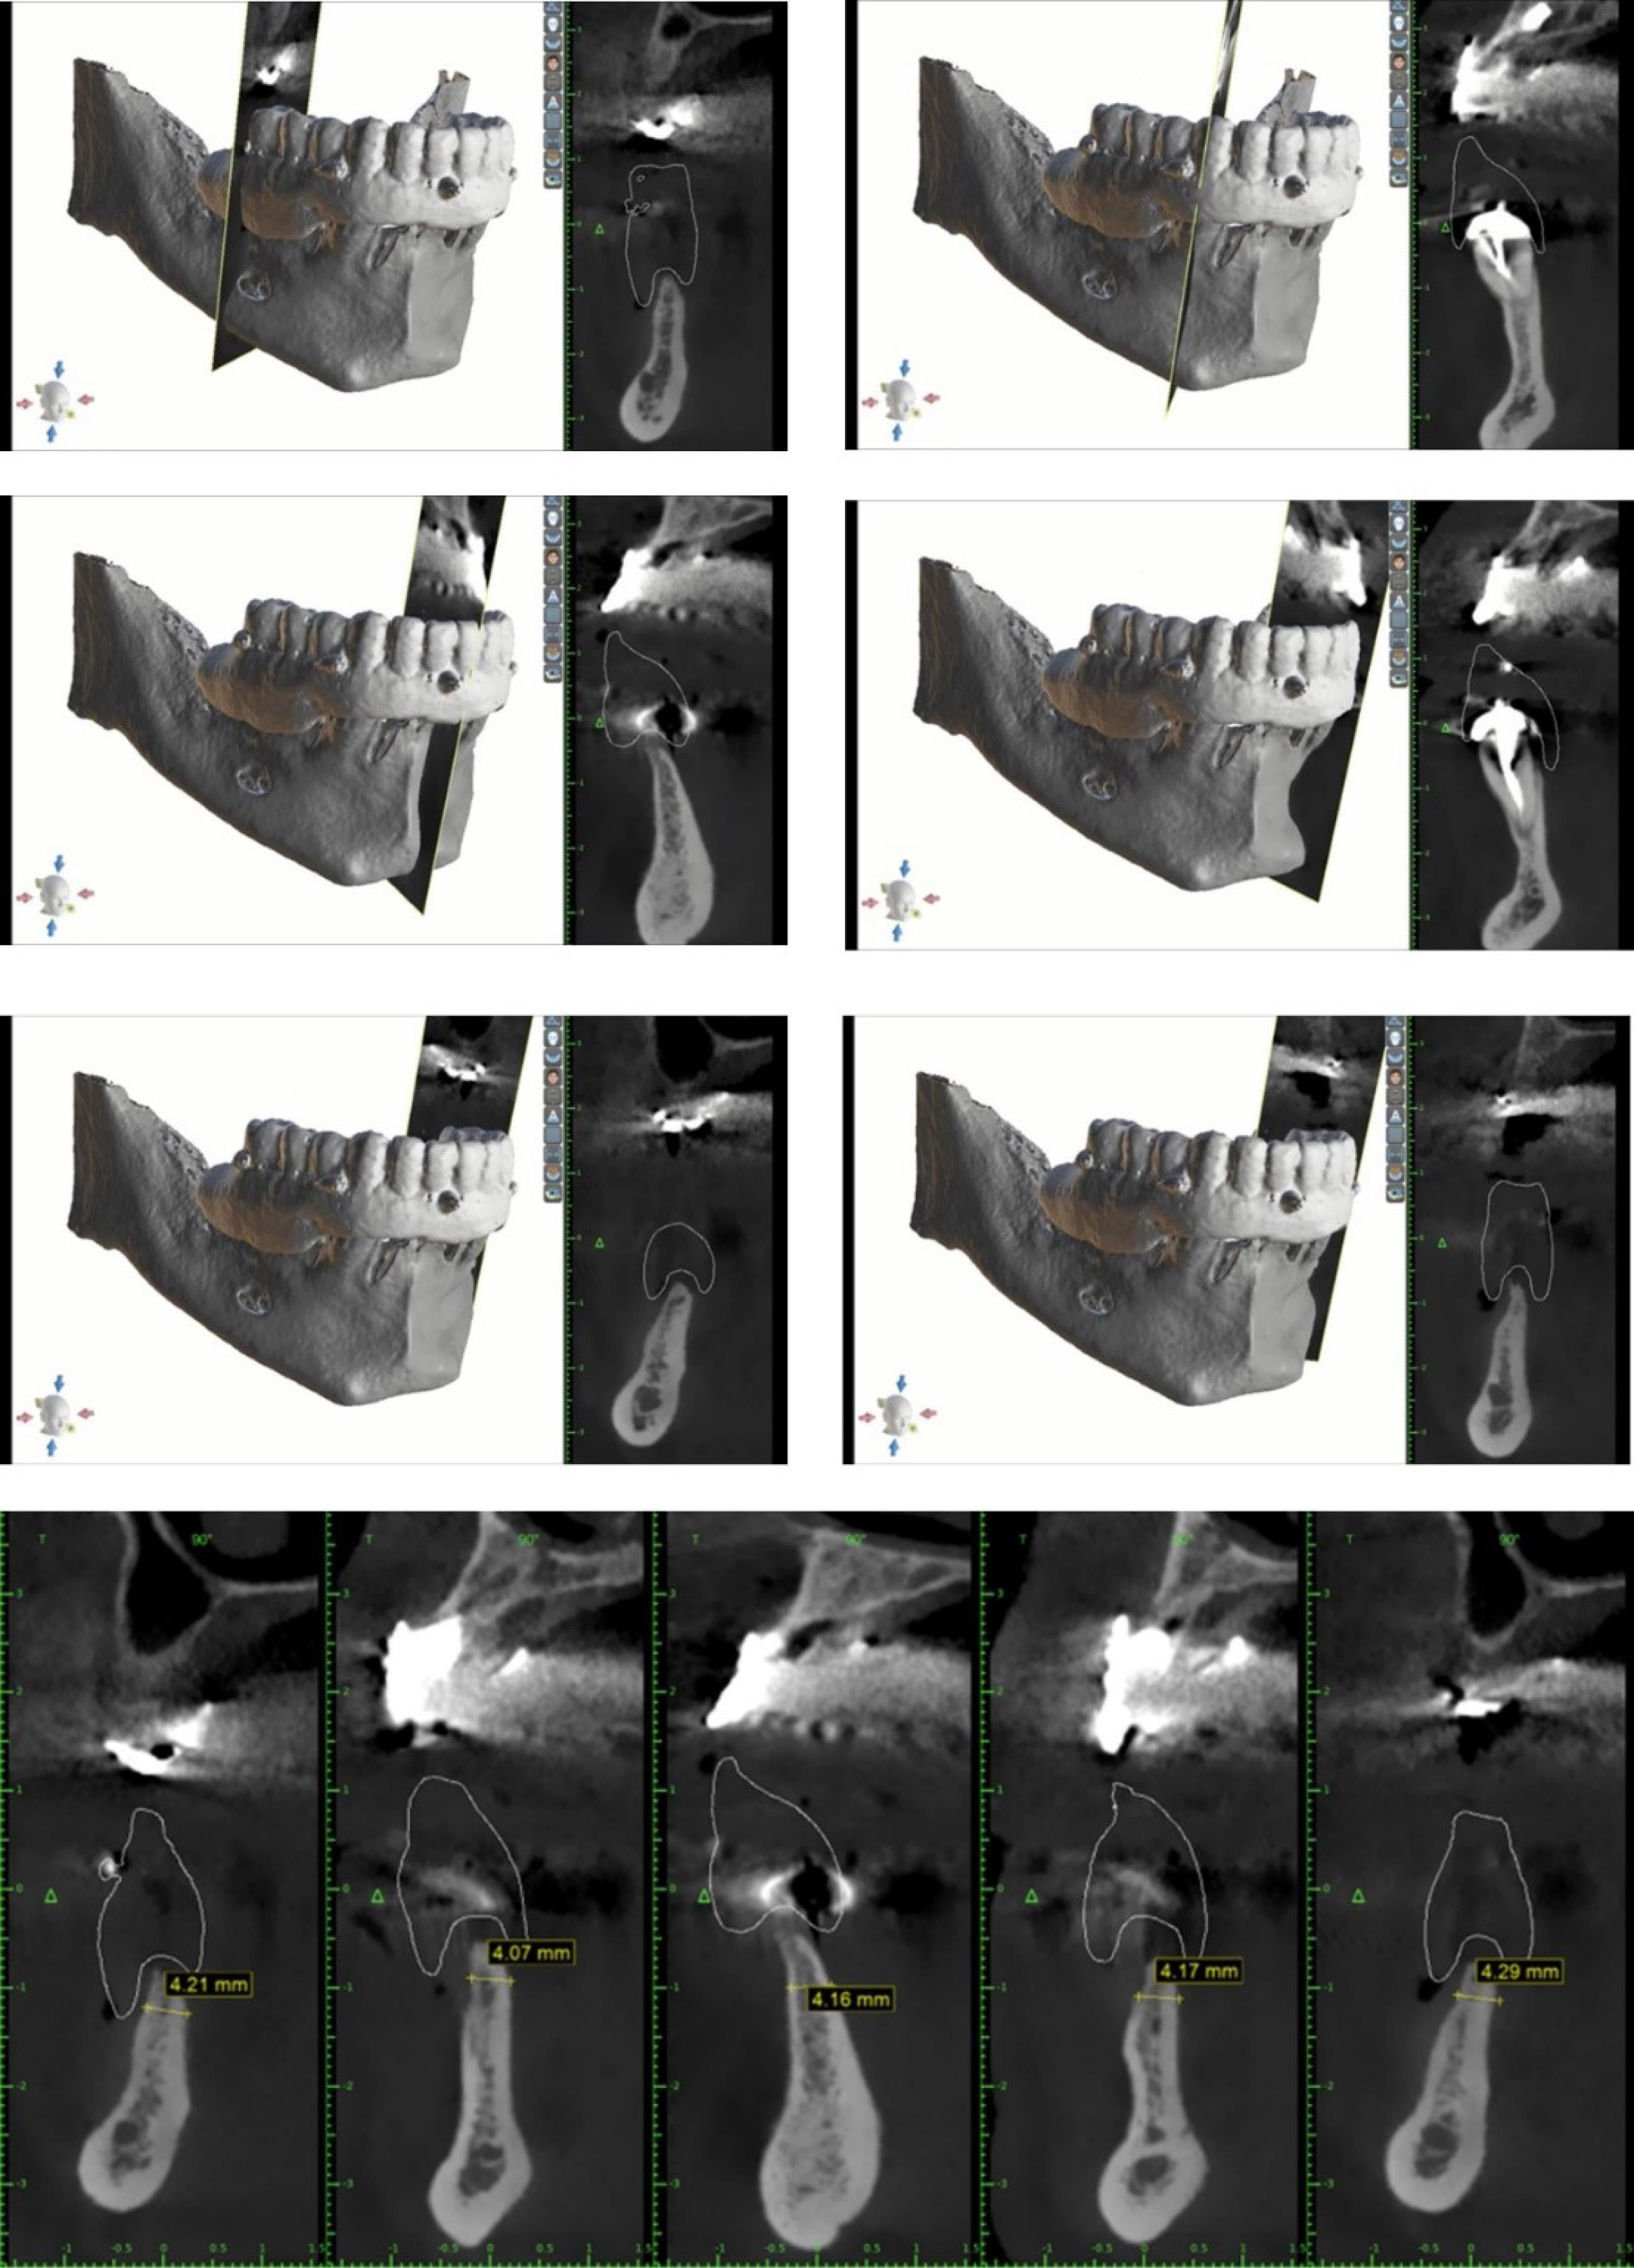

The present case report follows the CARE checklist (https://www.care-statement.org/checklist). A 60-year-old partially edentulous male patient, complaining of functional and aesthetic discomfort, visited our dental clinic. The patient wore an implant-supported bar-engaged removable denture in the upper jaw. At the same time, the mandible was rehabilitated with an overdenture retained by two ball attachments on the residual cuspid roots (Figure 2). A clinical intraoral examination showed an improvable occlusal relationship between the arches, with poor lower denture stability. The patient requested to be treated as quickly as possible and was willing to wear a fixed mandibular prosthesis immediately. After taking a panoramic x-ray, the occlusion was balanced, and a correct vertical dimension was achieved between the jaws by adjusting the overdentures. The inferior prosthesis was scanned, and the standard tessellation (STL) data were imported to the dedicated software. A cone-beam CT of the jaws was taken, and the relative DICOM files were digitally acquired and matched with the STL ones. The residual mandibular alveolar process appeared dramatically reduced in the horizontal dimension, with about a 5-mm thickness in the frontal and posterior zones (Figure 3). The option of the mini-implant was proposed to the patient since he firmly kept his decision to undergo one-session treatment despite being clearly warned about the unknown predictability of such an approach.

Figure 3.

CBCT slices after matching the bone data with the STL files from denture scanning. The adopted imaging software was 3D Romexis, Planmeka, Fin- 00880 Helsinki, Finland.